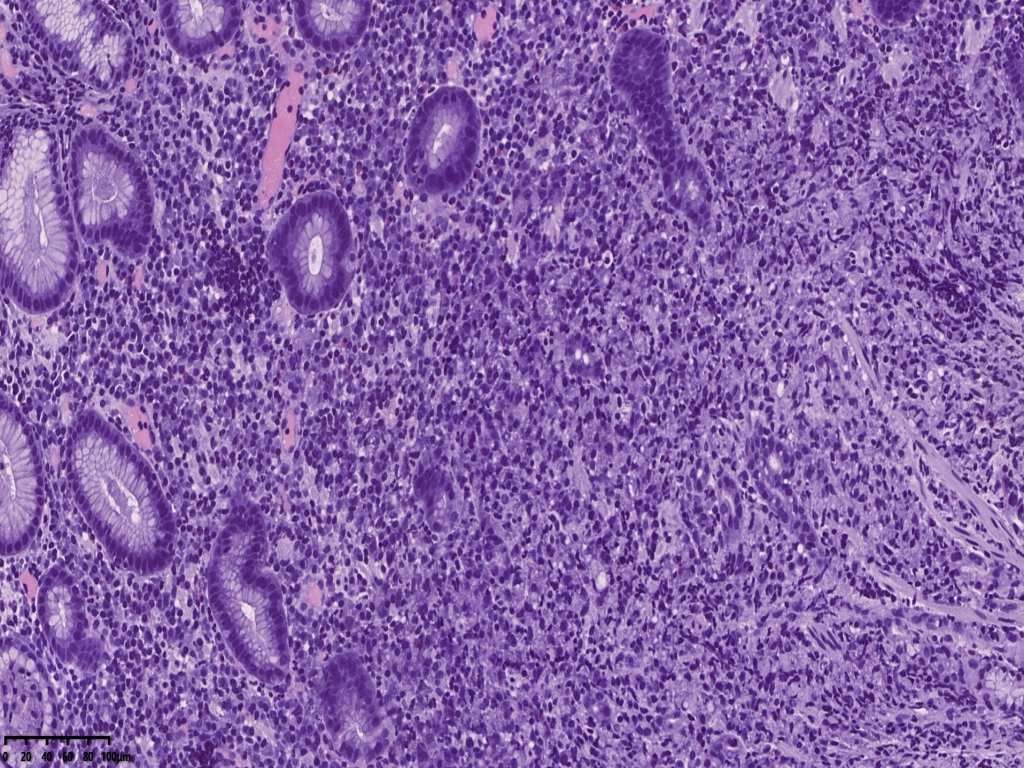

镜下可见胃活检组织,炎症背景明显,小凹及固有腺体结构大致正常,但是其中一块组织内固有层内可见小片状弥漫分布的上皮样异型细胞,组织细胞?浆细胞?溃疡直径大于1厘米,应首先除外肿瘤。